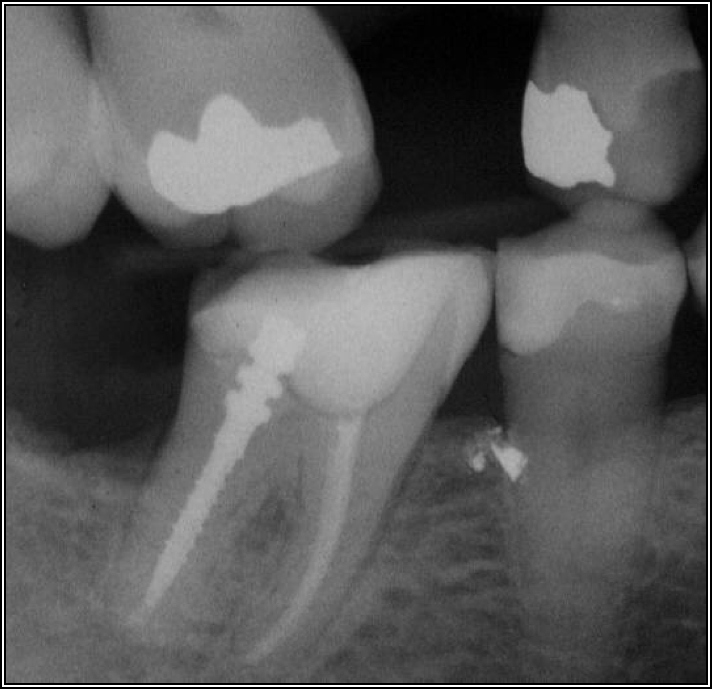

Occlusion is one of the most overlooked areas in endodontics; however, other than remaining structure, it is the most important factor.7 Patients who are heavy bruxers can cause the need for a root canal from the lateral forces. Patients who clench pose a different challenge with apical forces, yet the damage from both can be the same. Figure 7 shows a patient with bruxism. The patient had pain in response to hot and cold stimulus, and the clinicians needed a bitewing to determine which tooth was causing the pain. From the periapical (PA), it was clear that tooth No. 2 had a large problem, No. 3 had a crown, and No. 4 had a large restoration. Any of the three may have been the source of the problem.

With the bitewing shown in Figure 8, it became clear there was gross decay in tooth No. 3 that could not be seen on the PA, and there was a periodontal defect, a pulp stone, in No. 2. There was also a class V lesion revealing the bruxism, flat occlusion, multiple restorations in No. 30, a post in No. 31, and decay on No. 2 as well. The post in No. 31 was useless because when a post is placed, it must be the right length, width, and size. If the post is too short, there will be a greater fulcrum and the tooth will break. If it is too long, the clinician can break it by wedging it. If it is too short, it will not hurt the tooth, but it will not provide any valuable function. It is overall preferable to do posts in teeth having just single restorations rather than abutments for bridges because those teeth are already under greater force. If the technique is not performed correctly, iatrogenic issues may result.

Fig 7. Bruxism.

Figure 7

Fig 8. Bitewing revealed decay and other problems.

Figure 8